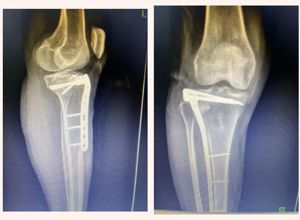

近日 我院骨外科二区在 科主任、主任医师李玉春的带领下 自主成熟开展 微创技术治疗复杂胫骨平台骨折 以小切口实现大疗效 标志着我院骨科诊疗技术迈上新高度 此前,胫骨平台骨折的传统治疗需采用大切口手术,存在创伤大、出血多、术后恢复慢等弊端,且术中无法直视胫骨平台平整度,这也是术后创伤性关节炎的主要诱因。骨...